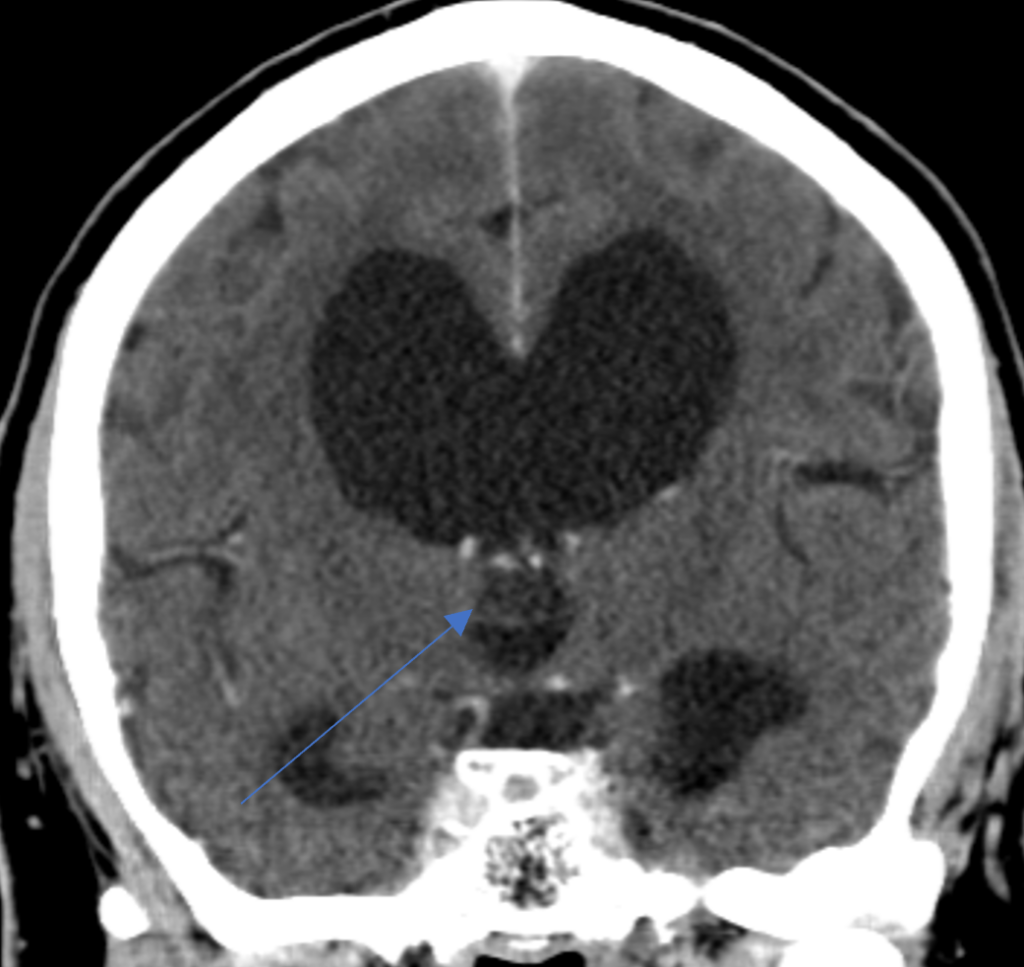

60-year-old woman with unilateral arm/leg weakness

60-year-old woman presented with unilateral arm/leg weakness.